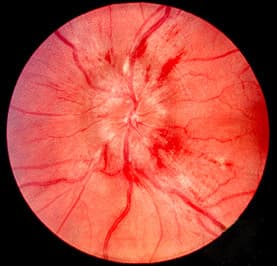

Papilledema or papilloedema is optic disc swelling that is caused by increased intracranial pressure due to any cause. The swelling is usually bilateral and can occur over a period of hours to weeks. Unilateral presentation is extremely rare. In intracranial hypertension, the optic disc swelling most commonly occurs bilaterally. When papilledema is found on fundoscopy, further evaluation is warranted because vision loss can result if the underlying condition is not treated. Further evaluation with a CT or MRI of the brain and/or spine is usually performed. Recent research has shown that point-of-care ultrasound can be used to measure optic nerve sheath diameter for detection of increased intracranial pressure and shows good diagnostic test accuracy compared to CT. Thus, if there is a question of papilledema on fundoscopic examination or if the optic disc cannot be adequately visualized, ultrasound can be used to rapidly assess for increased intracranial pressure and help direct further evaluation and intervention. Unilateral papilledema can suggest a disease in the eye itself, such as an optic nerve glioma. In the early stages, papilledema may be asymptomatic or present with a headache. It can progress to enlargement of the blind spot, blurring of vision, visual obscurations (inability to see in a particular part of the visual field for a period of time). Ultimately, total loss of vision can occur. The signs of papilledema that are seen using an ophthalmoscope include: venous engorgement (usually the first signs) loss of venous pulsation hemorrhages over and/or adjacent to the optic disc blurring of optic margins elevation of the optic disc Paton's lines (radial retinal lines cascading from the optic disc) On visual field examination, the physician may elicit an enlarged blind spot; the visual acuity may remain relatively intact until papilledema is severe or prolonged.